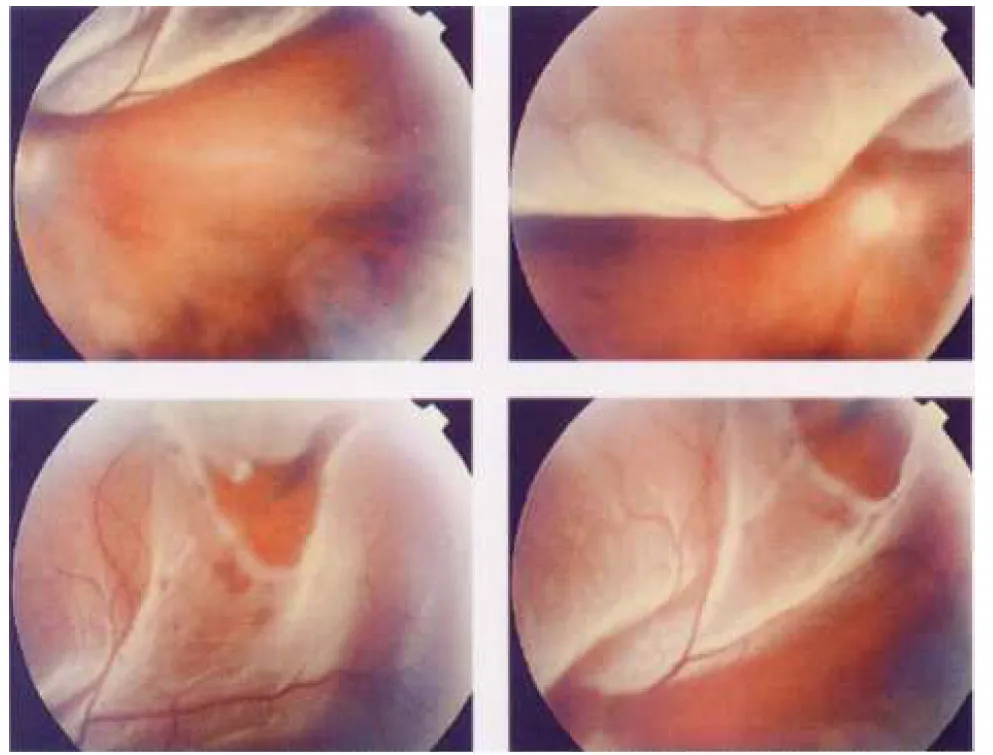

【108-2 醫學(六) 第17題】如眼底視網膜照片所示,此位患者最可能之診斷為何?

這張眼底照片最關鍵的線索是看到視網膜脫落後呈現蒼白、皺褶的狀態,並且在其中一張圖中能清楚看到一個紅色的視網膜裂孔,這直接指向裂孔型視網膜剝離。